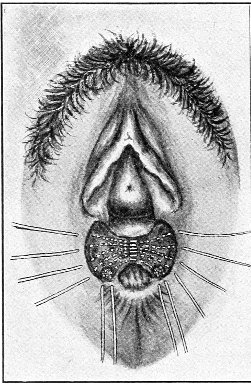

Suppuration of the vulvo-vaginal gland is accompanied by marked swelling and peripheral edema. The swelling may extend to the anus, and is of characteristic shape (Fig. 17). The pain is always severe. Fluctuation is first apparent on the inner surface of the labium majus. If the condition is not treated, one or more fistulous openings appear below the orifice of the duct, and the pus is discharged. The condition then becomes chronic. The fistulous openings persist. Acute inflammation disappears from the gland, leaving it in a condition of hypertrophic induration. A thin, milky or greenish, purulent fluid may be pressed out of the duct or the fistulous openings. Infection from this discharge may be communicated to man, or may ascend the genital 40 tract, producing inflammation of the endometrium or of the Fallopian tubes.

Fig. 17.—Abscess of right vulvo-vaginal gland.

In abscess of the vulvo-vaginal gland a free incision should immediately be made into the labium at the junction of the skin and the mucous membrane. The interior should be wiped out with pure carbolic acid and the cavity packed with gauze. If the disease is first seen in the chronic stage, after the abscess has evacuated itself, the only method of cure is to excise, with curved scissors, the whole of the indurated gland, the duct, and the fistulous tracts. The wound may be left open and packed, or it may be closed immediately with buried catgut sutures.